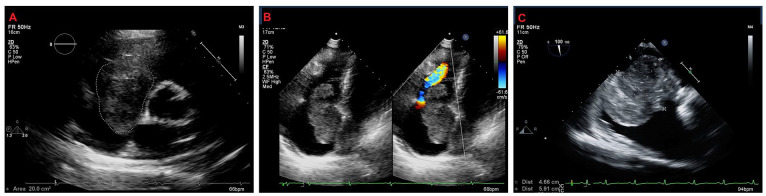

右心房黏液瘤是一种非常罕见的心脏肿瘤,可引起毁灭性的并发症。这些肿瘤能够通过静脉回流和三尖瓣流入阻塞而产生右侧心力衰竭。在此,我们描述了一位52岁的女性,表现为典型的rHF症状,为巨大RAM的临床后遗症。临床医生应认识到RAMs是rHF的非典型病因,在诊断检查和早期手术切除中补充成像方式是关键的管理策略。

Right atrial myxomas (RAMs) are exceedingly rare cardiac tumors that can incur devastating complications. These tumors are capable of producing right-sided heart failure (rHF) through obstruction of venous return and tricuspid inflow. Herein, we describe a 52-year-old woman presenting with classic symptomatology of rHF as clinical sequelae of a giant RAM. The clinician should be cognizant of RAMs as an atypical etiology of rHF, and the complementary imaging modalities in the diagnostic work-up and early surgical resection as key management strategies.